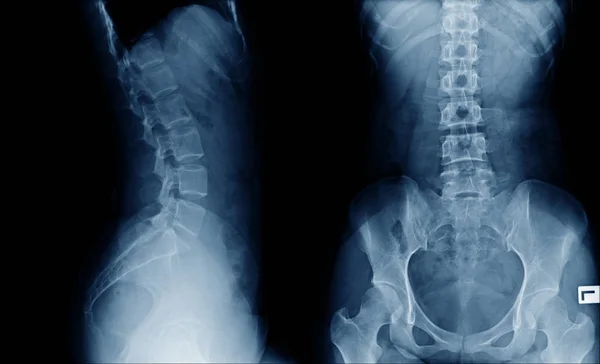

Sciatica is not a disease but a collection of symptoms including sharp or pricking pain, numbness, tingling, and weakness that begins in the lower back and radiates down through the buttocks, legs, and into the foot. The primary cause is the compression or irritation of the sciatic nerve, often due to a herniated disc, spinal stenosis, or injury.